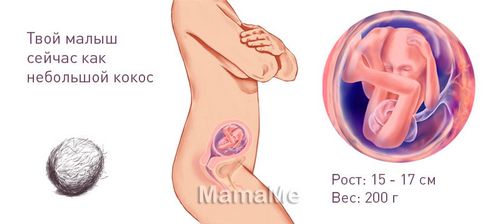

Плід на 19 тижні вагітності розвивається, набирає вагу (зараз це близько 200 грамів), зростає - (його зріст приблизно 15-17 см). У тілі крихти продовжує накопичуватися жировий прошарок - він готується до появи на світ. Активно розвивається і смоктальний рефлекс. Ступня дитини вже добре оформлена, її розмір зараз становить всього 2,5 см. В подальшому ніжка буде рости, але пропорції залишаться незмінними.